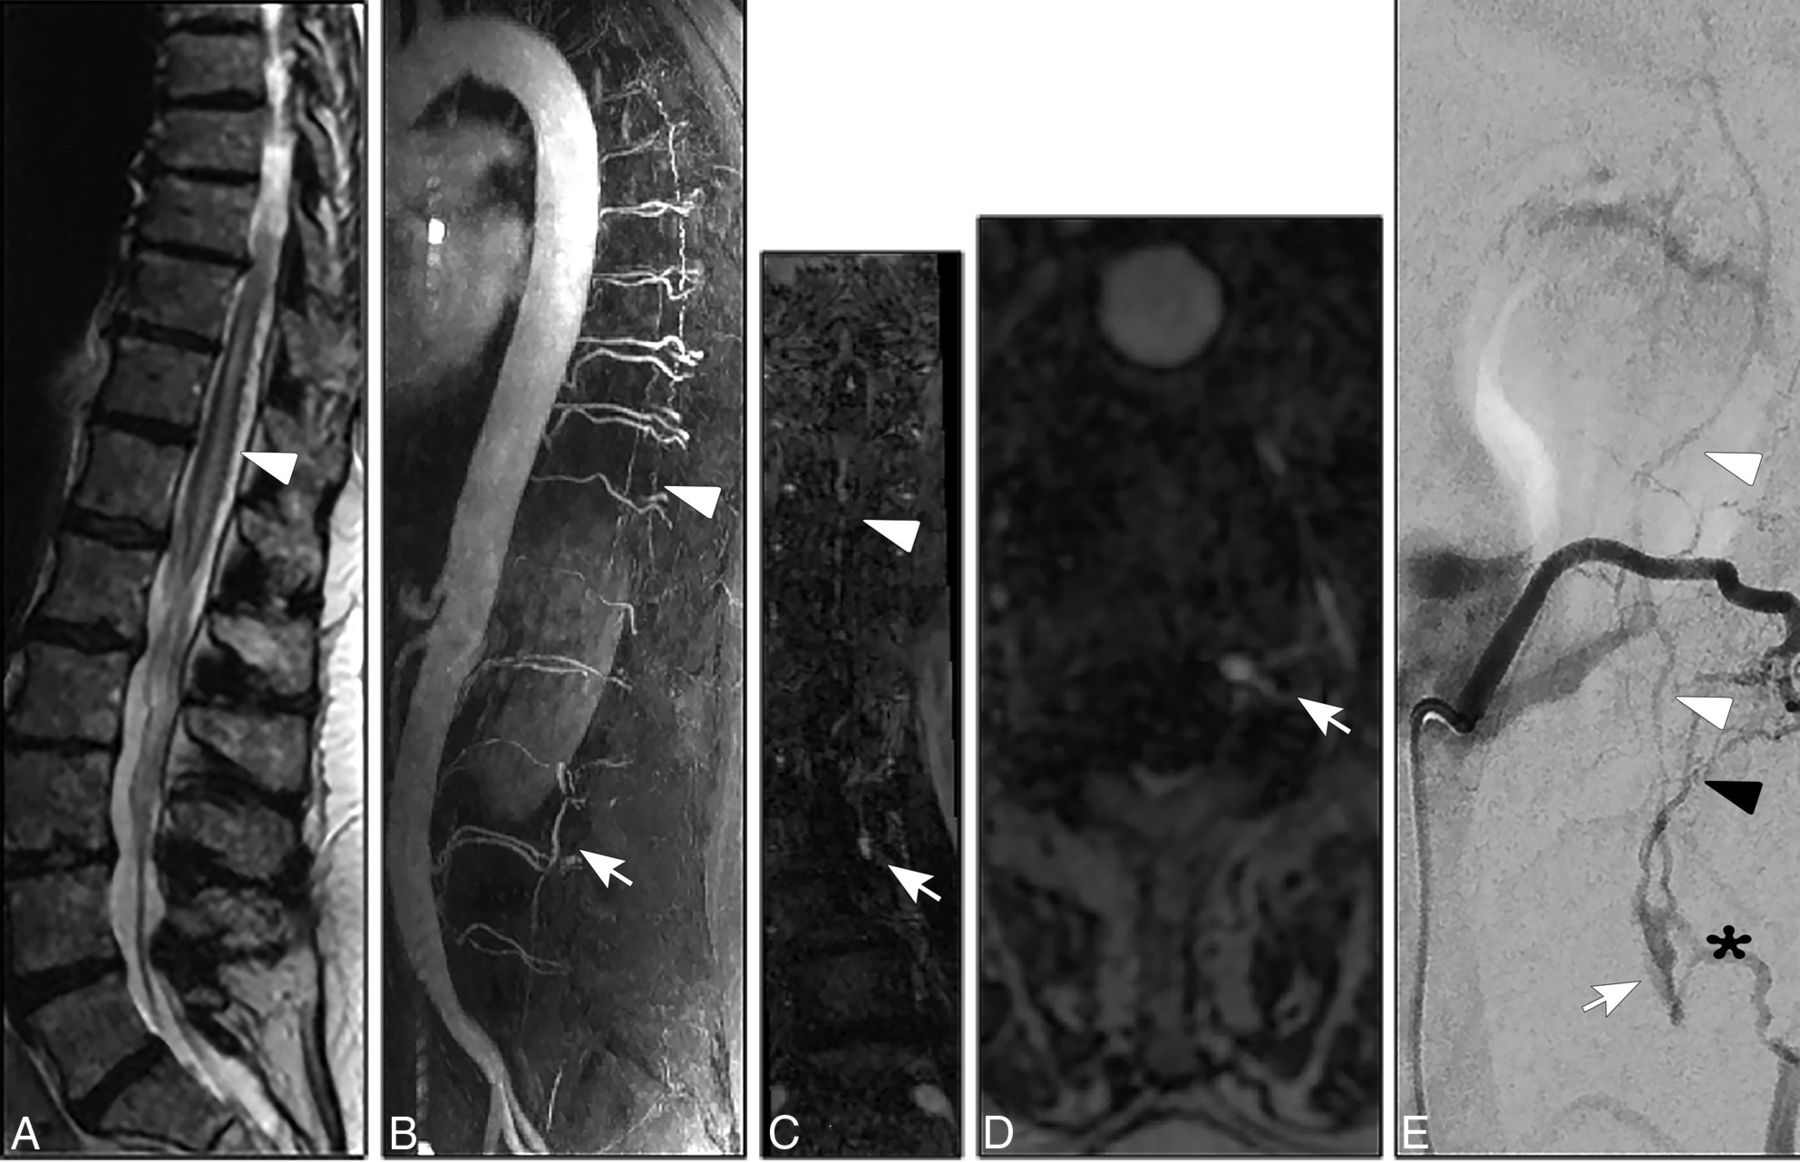

Concerning the location of the AV shunt, the fistulous zone in all our patients was in the ventral and ventrolateral epidural spaces with variable craniocaudal extension of the arterialized epidural pouch along several vertebral levels (Fig 1).

A, Sagittal T2- weighted images (3T; T2-TSE; slice thickness, 3 mm) reveal extensive congestive myelopathy (white arrowhead). B–D, Spinal CE-MRA (3T; time-resolved imaging with strochastic trajectories (TWIST); sagittal MIP; coronal and axial MPR) shows arterialized pouch in the lumbar ventrolateral epidural space (white arrows) in association with arterialized perimedullary veins in the thoracic region (white arrowheads) suspicious for a SEAVF in the lumbar region. E, DSA in lateral projection shows a SEAVF (white arrow) supplied via branches of the left L2 segmental artery (black arrowhead) and drained via the respective intradural radicular vein (white arrowheads). Note the extraspinal venous outlet (asterisk).